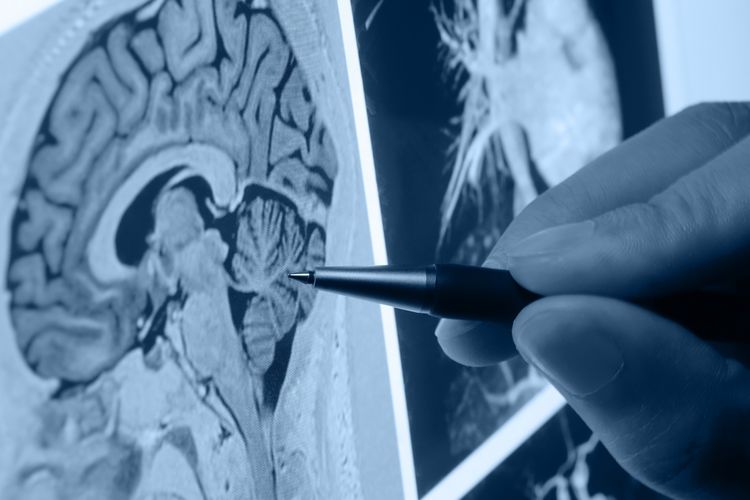

Специалисты клиники Acıbadem для постановки правильного диагноза используют современные диагностические средства, которые позволяют определить проблему в начальной стадии.

Лечением опухолей головного мозга занимается команда врачей, в состав которой входят радиологи, онкологи, неврологи, нейрохирурги и нейроанестезиологи. Их знания и опыт позволяют справляться с самыми сложными проблемами, выходить победителями в борьбе с болезнью. Оперативное вмешательство проходит с использованием передовых методик, применяются микроскоп, нейроэндоскоп, интраоперационная томография, интраоперационный магнитный резонанс, нейромониторинг.

Профессор Ильхан Эльмаджы делает акцент на нейромониторинге, поясняя, что в операционной, независимо от того находится пациент под наркозом или нет, идет непрерывная оценка электрической активности мозга. Параллельно проводятся нейрорадиологические исследования, что помогает точно определить местонахождение областей, ответственных за жизненно важные функции в организме, оценить работу мозга в целом. Мозг каждого человека обладает определенными особенностями, врач должен оценить их перед операцией. Новые технологии, использование специального программного обеспечения позволяют это сделать. Нейрорадиологи могут точно указать, какие области отвечают за различные функции в организме, определить место локализации опухоли. На основании полученных данных проводим анализ, что облегчает проведение операции в каждом отдельном случае. Благодаря нейромониторизации значительно снижается риск повреждения тех тонких структур мозга, которые невозможно увидеть невооруженным глазом.